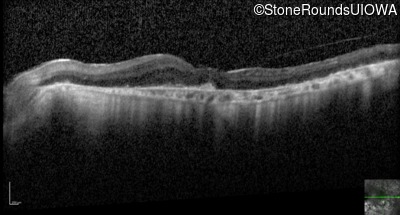

Optical Coherence Tomography - Left - 20/63 +2

Exemplar / OCT Stack

OCT Stack